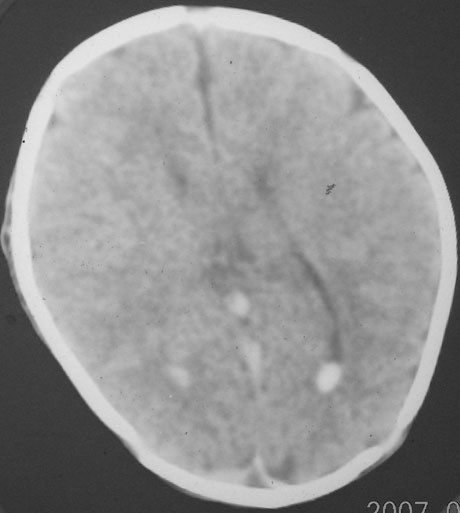

以下是引用rjg199343在2007-1-24 23:08:00的发言:[br]纵裂池、小脑幕、双侧脑室内高密度影,符合脑室、蛛网膜下腔出血。